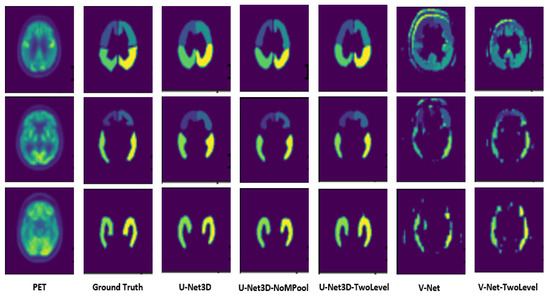

- U-Net3D, which is the original architecture composed of three encoder and decoder layers (Figure 2a);

- U-Net3D-NoMaxPoolingThirdDimension, where, for each layer, MaxPooling is not applied to the third dimension (Figure 2b). The network acquires more information for each layer, and a higher number of parameters must be estimated during the training phase;

- U-Net3D-TwoLevel (Figure 2c), which is a model characterized by eliminating one layer from the original architecture, reducing the number of parameters.

2.3.2. V-Net